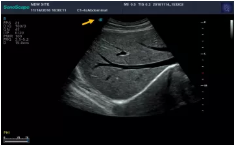

1、要避免氣體的干擾,比如在某些空腔臟器和深部組織檢測(cè)時(shí)充盈液體,如飲水后充盈胃腔以清除胃內(nèi)氣體,便于觀察胃腔內(nèi)的病變或以此為“透聲窗”觀察胰腺等;同時(shí),必須充分涂耦合劑以清除探頭與皮膚間薄層氣體,減少聲能的衰減;

2、利用某些生理解剖特點(diǎn)進(jìn)行觀察。如:空腹時(shí)膽囊內(nèi)膽汁充盈,便于觀察膽囊內(nèi)病變;又如呼吸配合,必要時(shí)可利用Valsalva動(dòng)作使肺內(nèi)與胸內(nèi)壓升高,以減少靜脈回流從而可使肝靜脈和下腔靜脈顯示清晰。